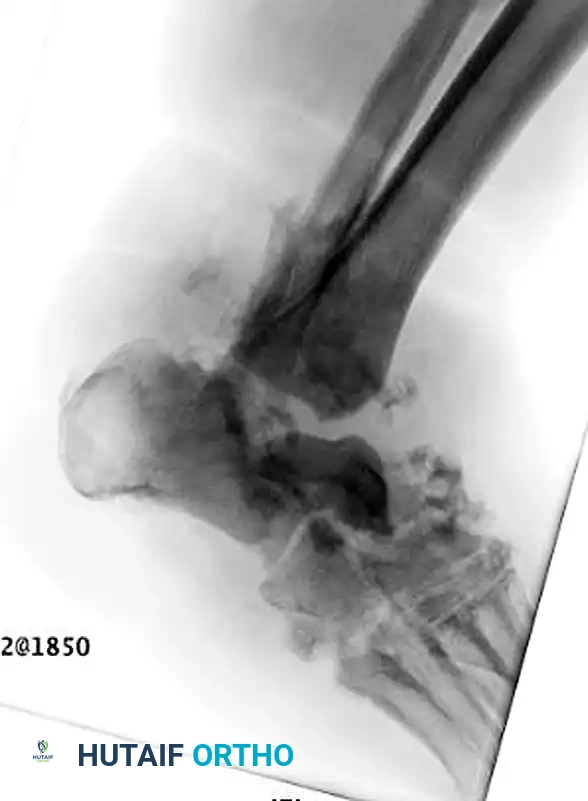

صورة شعاعية توضح انهيار مفاصل ليزفرانك وتشوه القدم

تعتبر الأشعة السينية الأداة الأساسية لتقييم حالة العظام. في المراحل المبكرة، قد تبدو الأشعة السينية طبيعية، ولكن مع تقدم المرض، تظهر علامات تفتت العظام، وخلع المفاصل، وتكون عظام جديدة بشكل غير طبيعي.

توضيح لخلع المفاصل وتفتت العظام في قدم شاركو

صورة تظهر قصر وانحراف العظام في القدم المصابة

أشعة سينية أمامية وجانبية تظهر تدمير المفاصل الرصغية المشطية

صورة تظهر تشوه القدم والتغيرات العظمية الشديدة